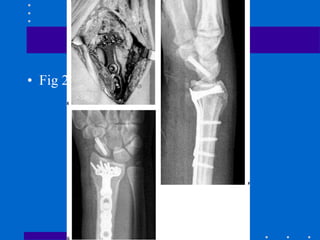

Fixação Externa

+ Redução aberta e fixação

interna

• Cominuição dorsal e volar de alta energia,

fragmentos não permitindo fixação interna

somente

• Varias coortes com sucesso

• Evita abordagem dupla dorsal e volar

• Figura 26-22